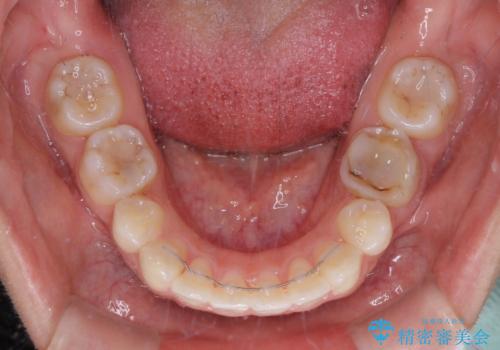

上顎抜歯のみでは奥歯の咬み合わせを改善することが困難であったため、途中で下顎小臼歯も抜歯をしました。

抜歯のタイミングが遅れると治療期間が長期化するため、速やかに抜歯の判断をし、2年強の期間で治療を終えることができました。